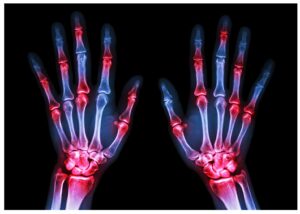

מהי דלקת פרקים?

הפרעת דלקת פרקים נובעת בדרך כלל

מריקבון של שכבות סחוס הפזורות בין המפרקים.

בפשטות, דלקת פרקים היא מחלה שתוקפת

ישירות את המפרקים, שבהם שתי עצמות נפגשות

או מתחככות בעזרת שכבת סחוס על מנת ליצור שלד

מאורגן כדי לספק תמיכה נאותה ליציבת גוף האדם.

סחוס הוא שכבת הגנה המספקת מגן בין שתי העצמות

בנקודת החיבור ומונעת מהן להתחכך זו בזו.

דלקת מפרקים שגרונית (RA)

במקרה זה, הפרעת דלקת פרקים מקורה

בהתקפות עוקבות של דלקת מפרקים שגרונית

על המערכת החיסונית של הגוף.

כתוצאה מכך, הוא פוגע ברקמות ובגידים

הנמצאים במפרקים השונים של גוף האדם.